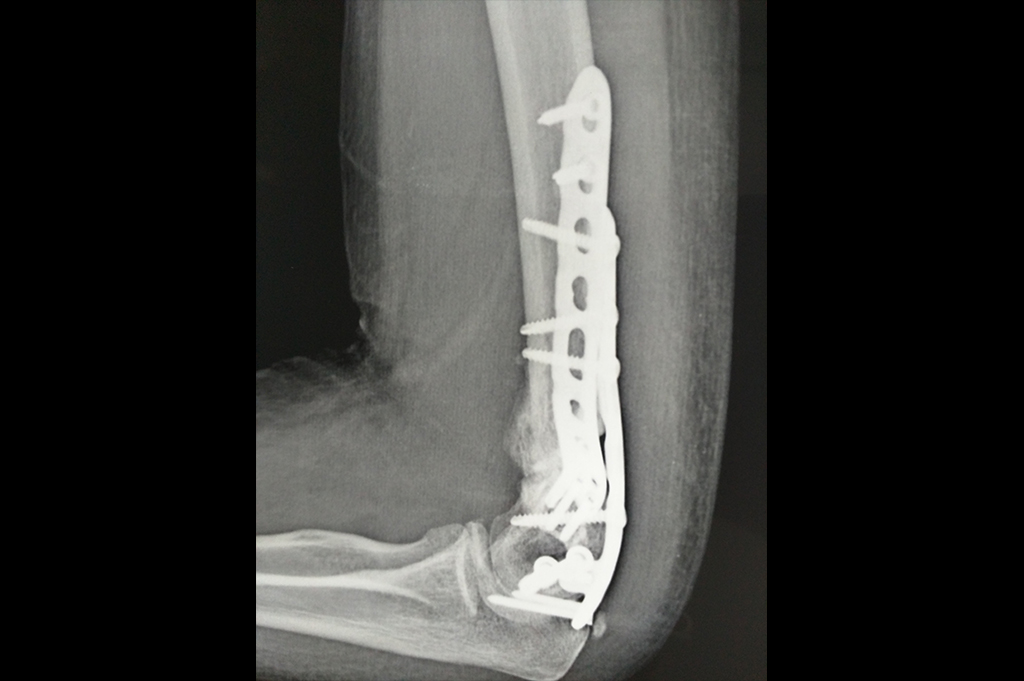

Periprosthetic Fracture THR